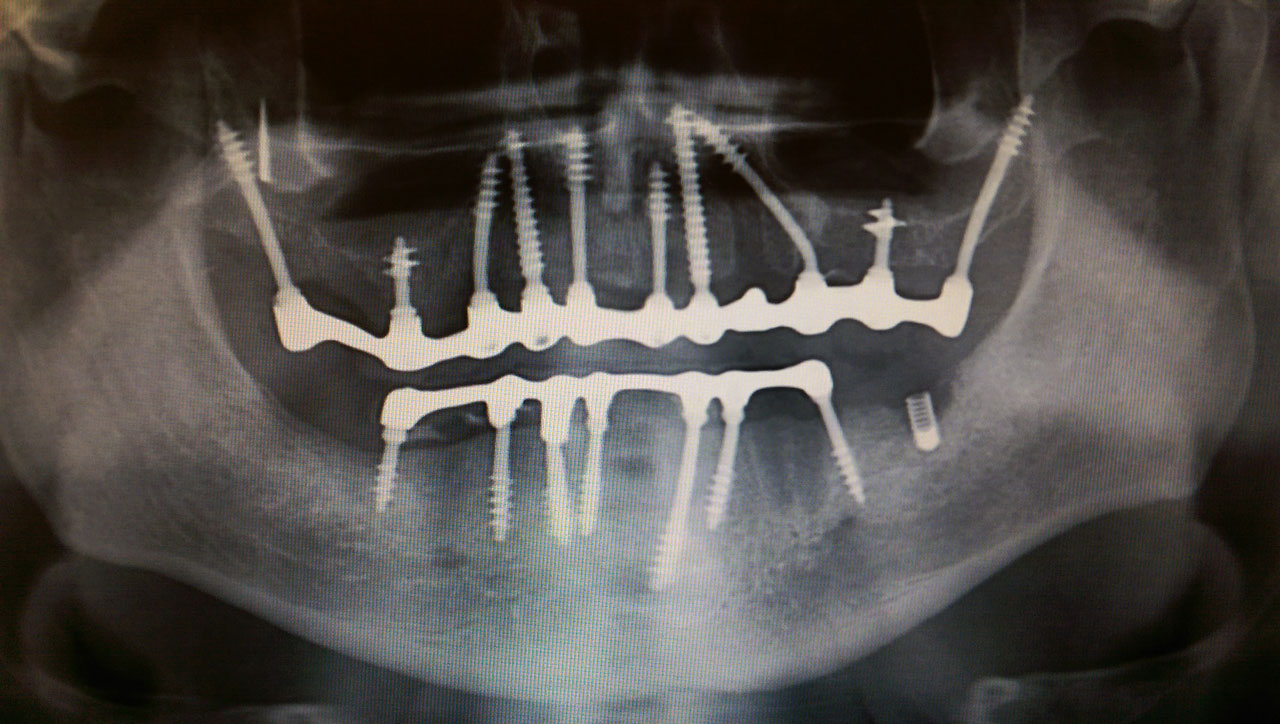

Elhanyagolt fogsor cseréje 2 nap alatt

2 nap alatt varázsoltuk ezt a szép esztétikus alsó, felső körhídat implantátumokkal megtámasztva a korábban elhanyagolt szájba. Az 1. nap 26 fogat távolítottunk el, mert annyira rossz állapotban voltak, és rögtön azonnal terhelhető IHDE svájci implantátumokat raktunk be, fentre 8, lentre 6 darabot. A sebeket összevarrtuk és intraorális szkennerrel digitális lenyomatot vettünk. 2 nap múlva pedig beragasztottuk a kész PMMA műanyag körhidakat. Dr. Kelemen Péter és a Symbion Fogtechnika munkája.